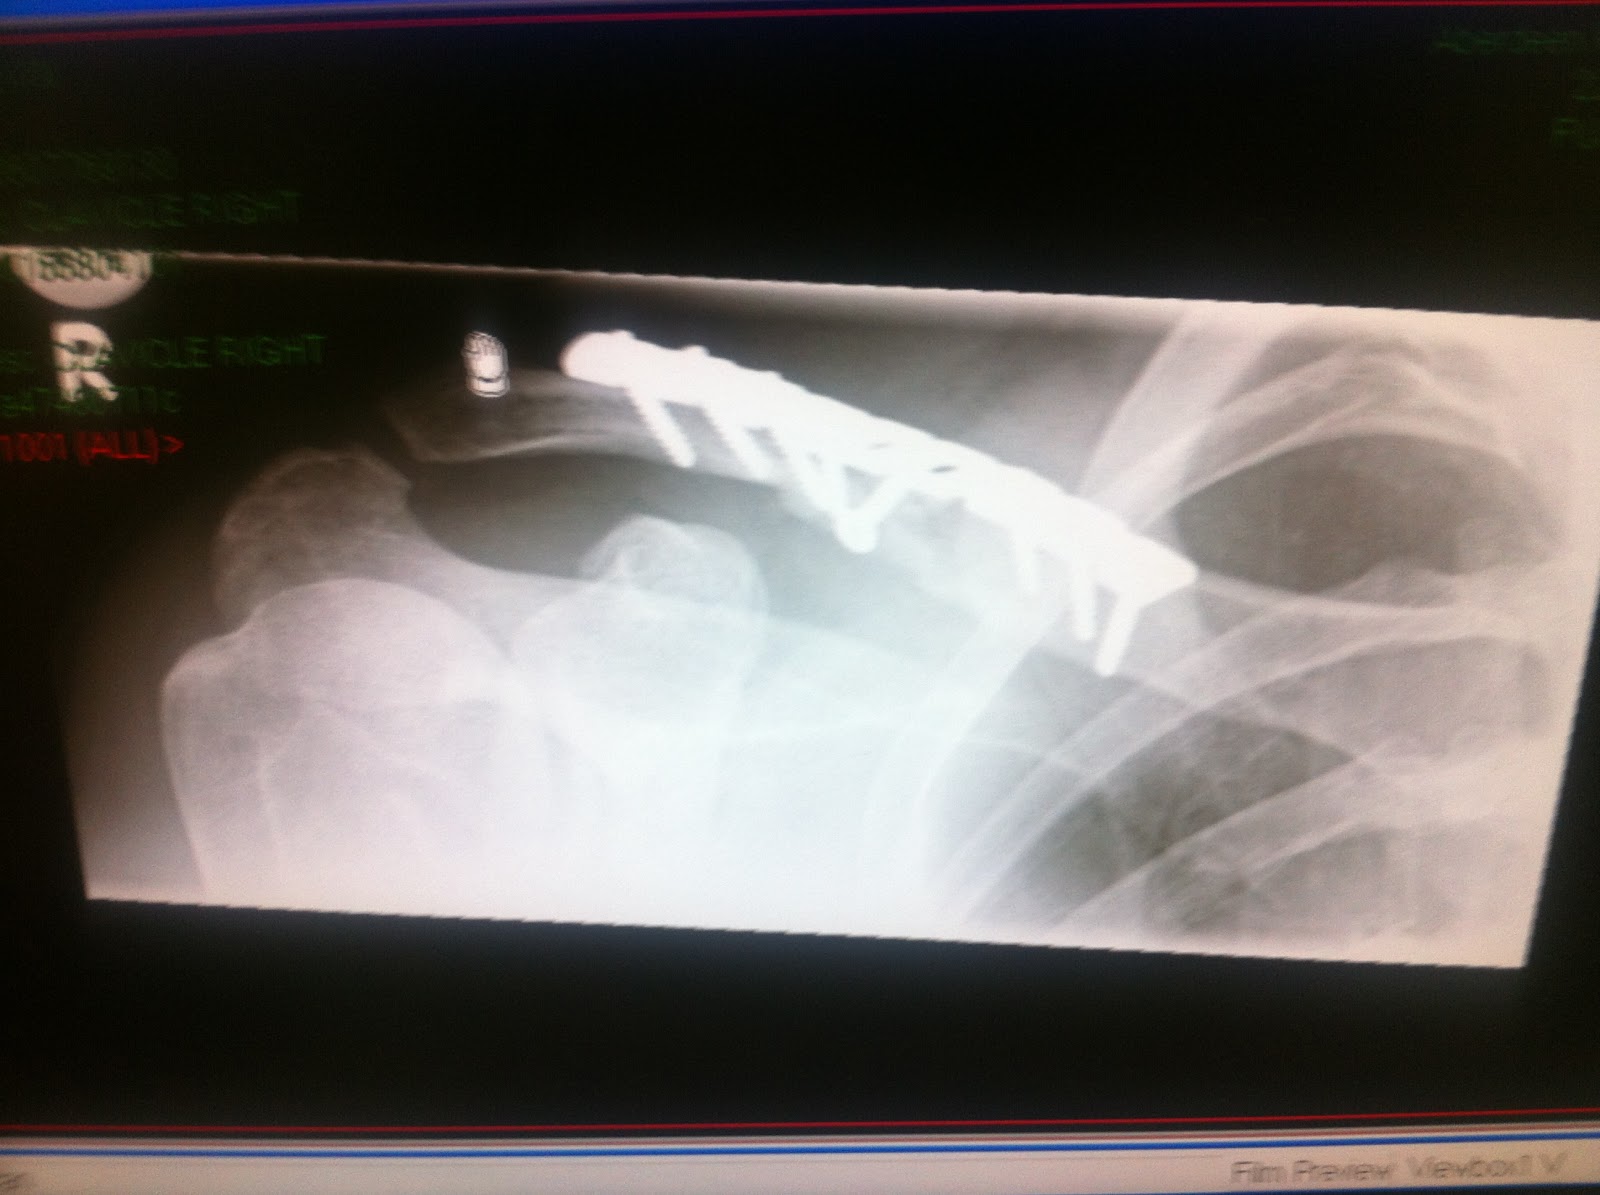

They kept me pretty heavily drugged through the night but I was able to get up and dress myself on friday morning. They let me have breakfast and lunch. Sent me for some x-rays of the plate (below) and then let me out.

Below is the latest x-ray. It is from December 3rd. It is a slightly different angle (serenity view for any medics in the audience) from the previous x-rays, so you can see the shape of the pin and the remaining smaller chip is more obvious.